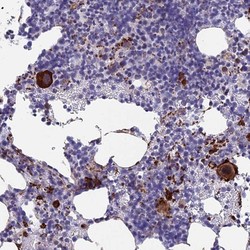

- Immunohistochemistry-Paraffin: C15orf59 Antibody [NBP1-93545] - Staining of human bone marrow shows strong cytoplasmic positivity in megakaryocytes.